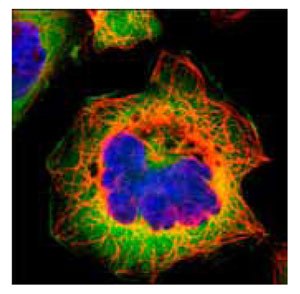

Anti-FASN.Product No. HPA006461: Immunofluorescent staining of human cell line A-431 shows positivity in cytoplasm.